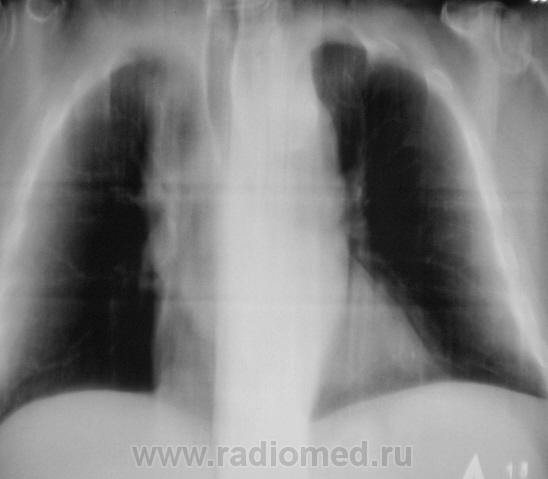

А на ЛГМ не похоже?

Похоже

Ну конечно, все правильно, при нео верхнего средостения - думаем о ЛГМ...

Лимфома, лимфосаркома не в счёт???

Ну, что-т о написать все одно надо. На мой взгляд скиалогия ЛГМ ближе. Слово за биопсией